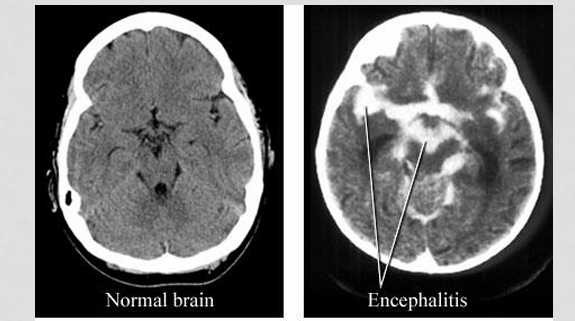

What is encephalitis?

inflammation of the brain

When encephalitis is suspected we usually do a lumbar puncture, viral testing, and radiologic imaging. What are some of the hallmark findings on an MRI that point towards a diagosis?

significant edema and hemorrhage within the temporal lobes